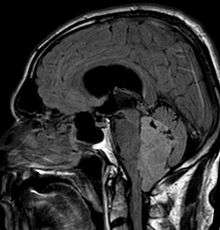

Ependymoma is a tumor that arises from the ependyma, a tissue of the central nervous system. Usually, in pediatric cases the location is intracranial, while in adults it is spinal. The common location of intracranial ependymoma is the fourth ventricle. Rarely, ependymoma can occur in the pelvic cavity.

Ependymomas make up about 5% of adult intracranial gliomas and up to 10% of childhood tumors of the central nervous system (CNS). Their occurrence seems to peak at age 5 years and then again at age 35. They develop from cells that line both the hollow cavities of the brain and the canal containing the spinal cord, but they usually arise from the floor of the fourth ventricle, situated in the lower back portion of the brain, where they may produce headache, nausea and vomiting by obstructing the flow of cerebrospinal fluid. This obstruction may also cause hydrocephalus. They may also arise in the spinal cord, conus medularis and supratentorial locations.[4] Other symptoms can include (but are not limited to): loss of appetite, difficulty sleeping, temporary inability to distinguish colors, uncontrollable twitching, seeing vertical or horizontal lines when in bright light, and temporary memory loss. It should be remembered that these symptoms also are prevalent in many other illnesses not associated with ependymoma.

About 10% of ependymomas are benign myxopapillary ependymoma (MPE). MPE is a localized and slowly growing, low-grade tumor. Although some ependymomas are of a more anaplastic and malignant type, most of them are not anaplastic. Well-differentiated ependymomas are usually treated with surgery. For other ependymomas, total surgical removal is the preferred treatment in addition to radiation therapy. The malignant (anaplastic) varieties of this tumor, malignant ependymoma and the ependymoblastoma, are treated similarly to medulloblastoma but the prognosis is much less favorable. Malignant ependymomas may be treated with a combination of radiation therapy and chemotherapy. Ependymoblastomas, which occur in infants and children younger than 5 years of age, may spread through the cerebrospinal fluid and usually require radiation therapy. The subependymoma, a variant of the ependymoma, is apt to arise in the fourth ventricle but may occur in the septum pellucidum and the cervical spinal cord. It usually affects people over 40 years of age and more often affects men than women.